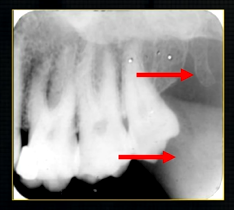

periapical radiograph → posterior maxilla

radiolucent maxillary sinus and radiopaque floor

radiopaque shadow cast by zygoma, hollowed out by maxillary sinus

lower end of the dense, zygomatic bone

posterior aspect of the maxilla - smooth round tuberosity